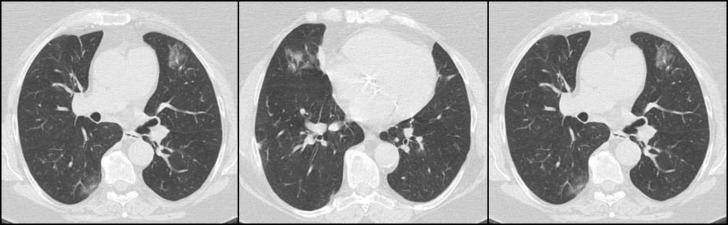

From March 17 to April 23, 2020, a total of 143 kidney transplant recipients were contacted. Twenty-eight patients needed in-hospital consultation for problems unrelated to COVID-19, 3 of whom needed hospitalization. Eleven patients were managed at home for mild urinary or respiratory diseases, and 1 was referred to the hematologist. We identified 2 suspected cases of COVID-19 infection, and the patients were referred to hospital care. Immunosuppressive therapy was modulated, and intravenous corticosteroids and potentially effective antiviral therapy were administered with a favorable outcome.

2020年3月17日至4月23日,共联系了143名肾脏移植受者。28名患者因与COVID-19无关的问题需要住院咨询,其中3人需要住院治疗。11名患者因轻度泌尿系统或呼吸系统疾病在家中接受治疗,1名患者被转诊至血液科医生处。我们发现了2例疑似COVID-19感染病例,并将患者转诊至医院治疗。调整了免疫抑制治疗方案,并给予静脉注射皮质类固醇和可能有效的抗病毒治疗,结果良好。